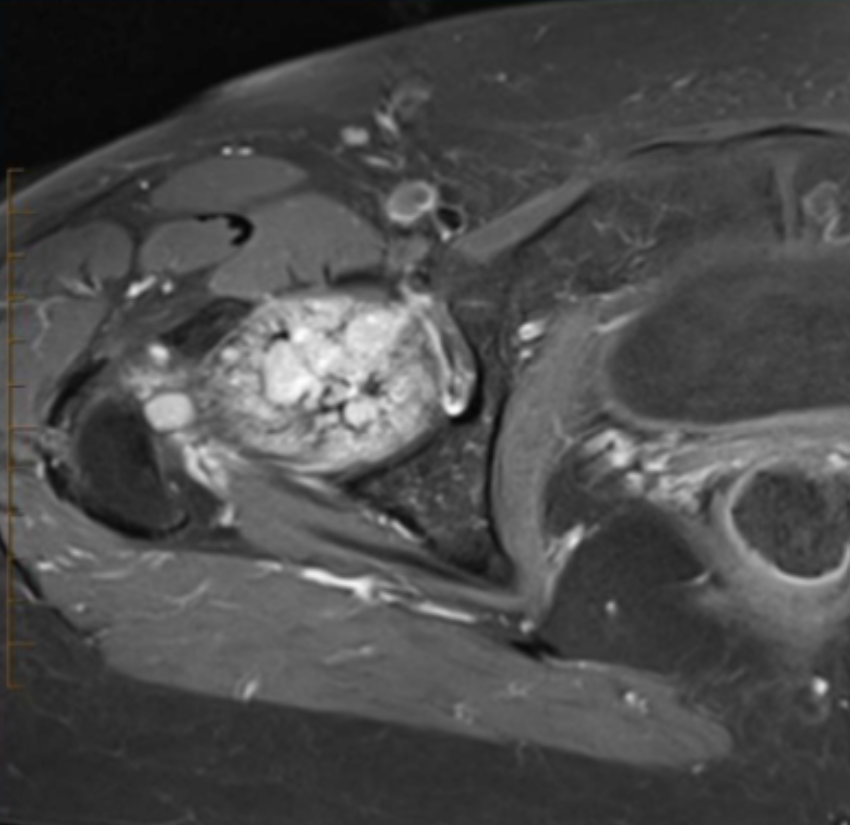

Describe the pathology (hint: it’s bone) (Ax T1 FS +C).

Osteochondroma